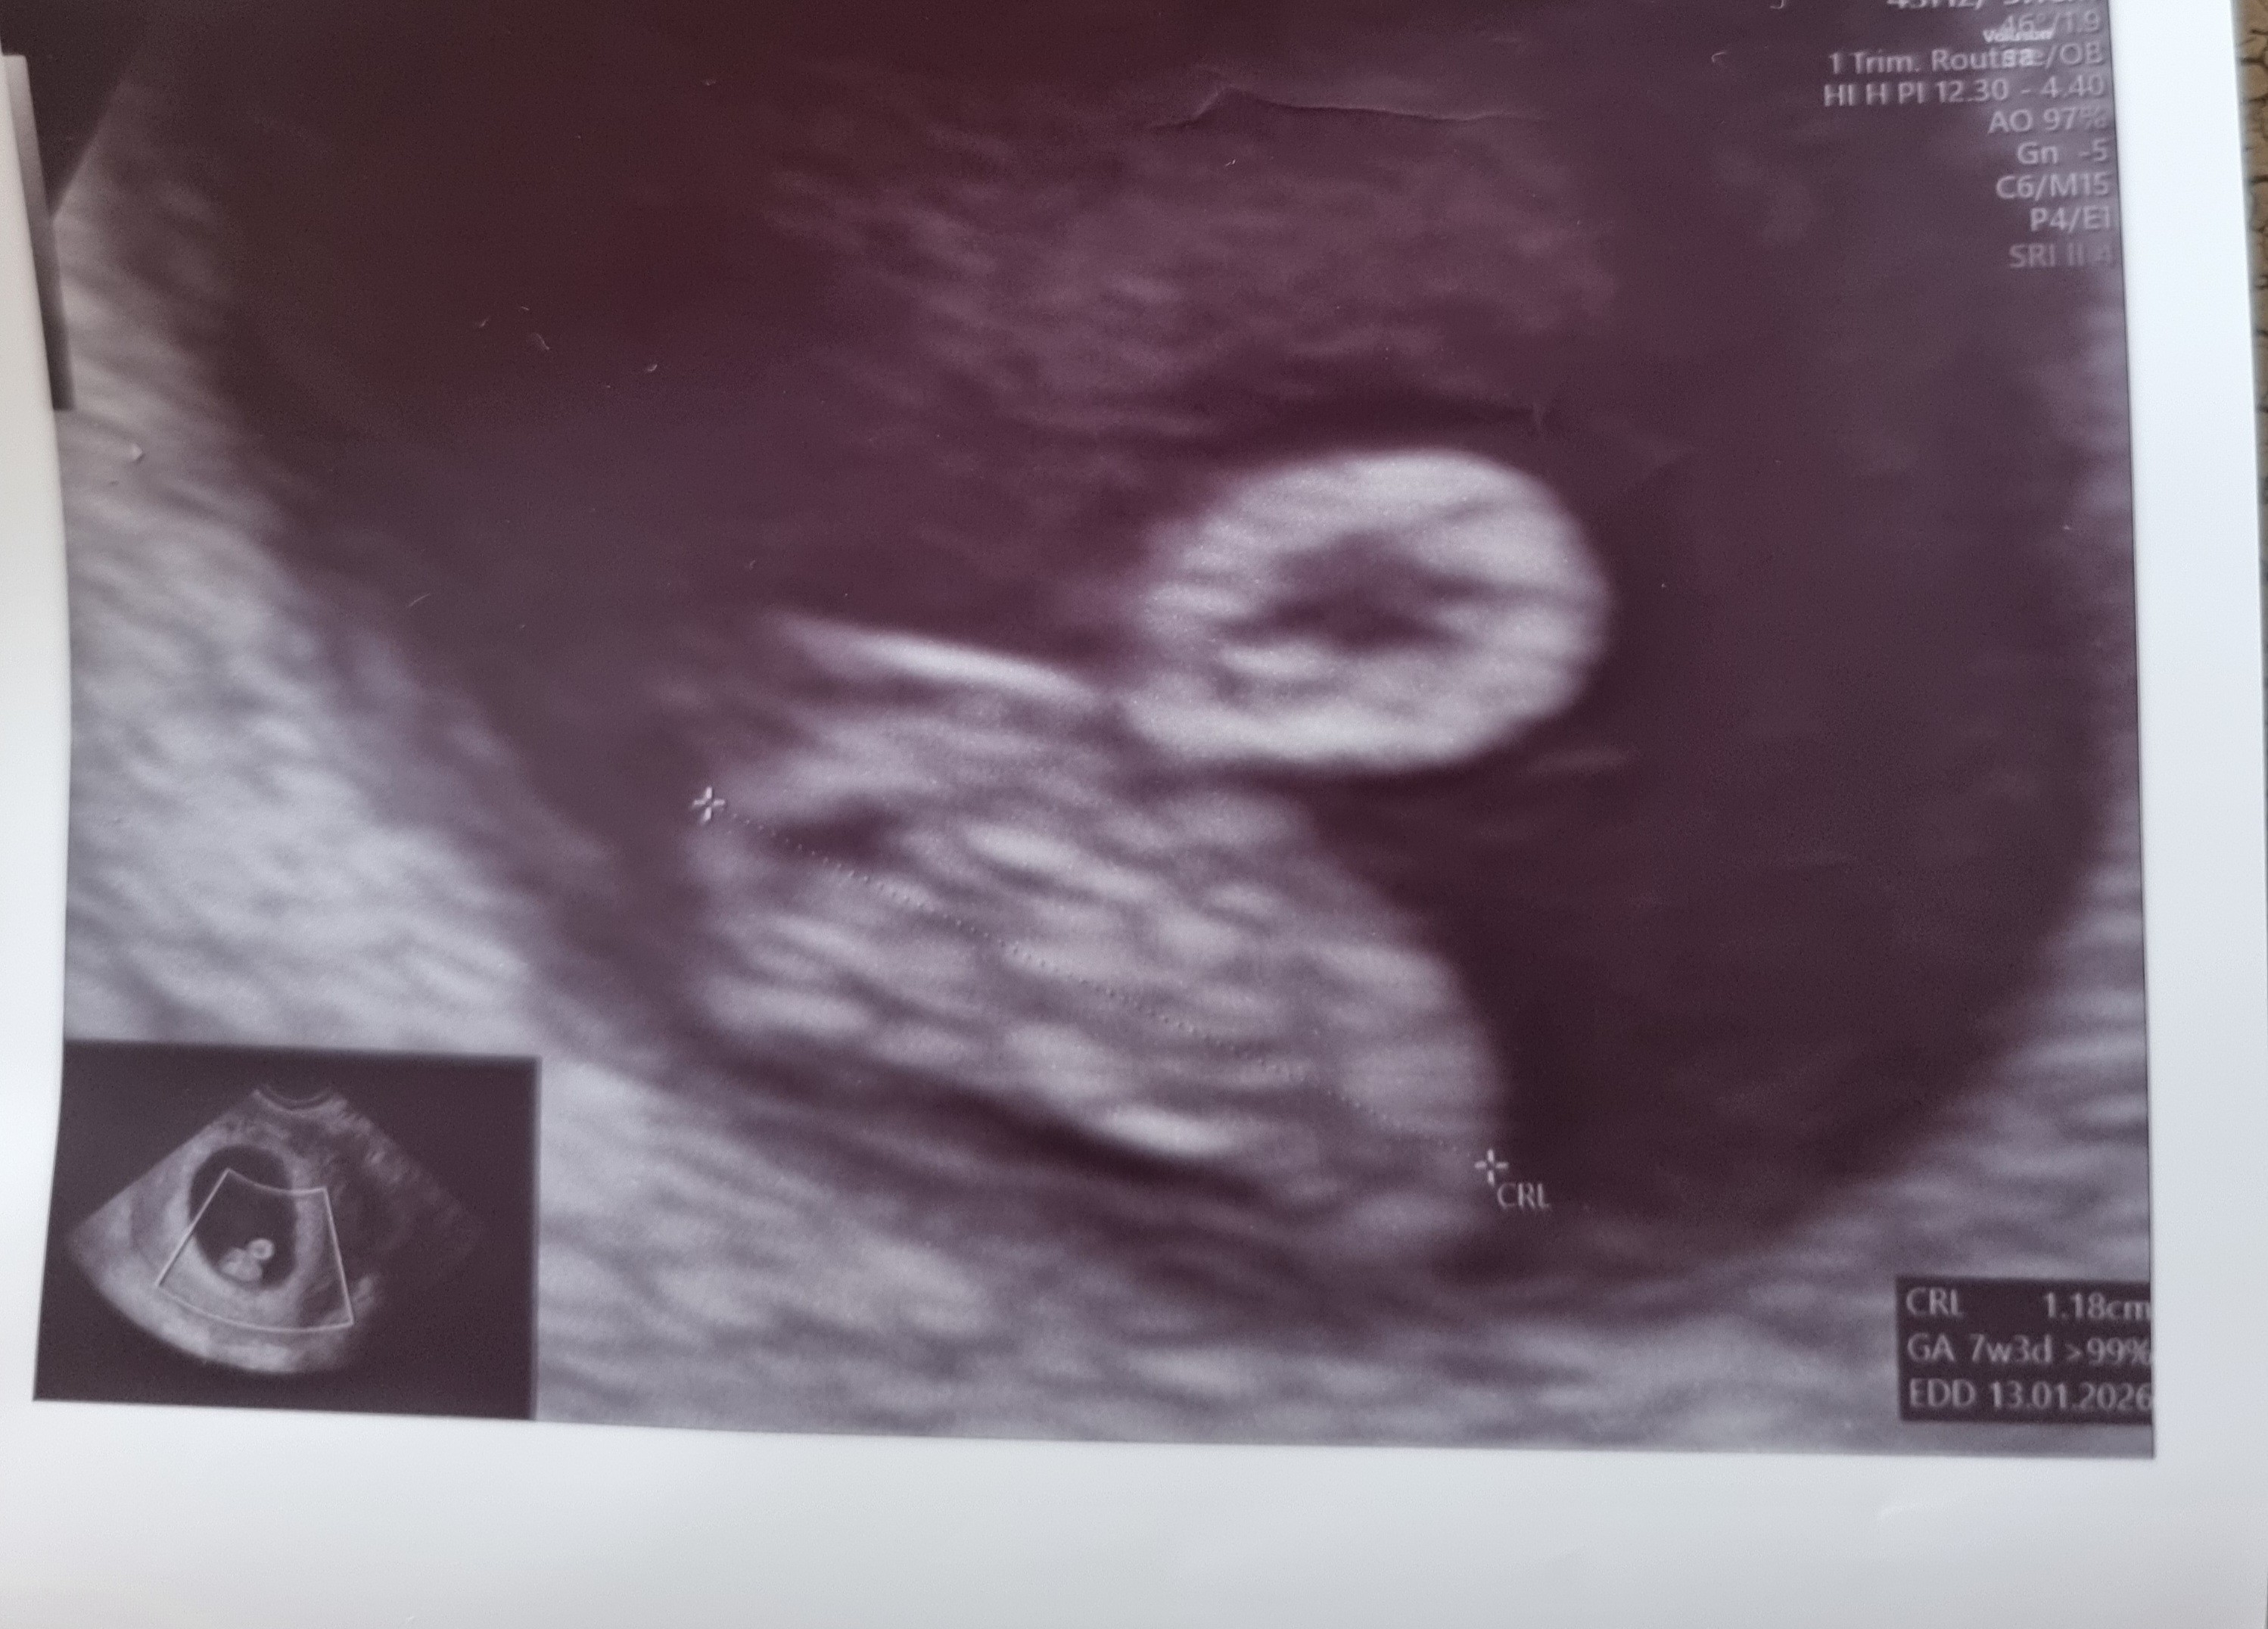

Mamy małą fasolkę, trochę starsza wg USG, ale później się wyrówna pewnie, z bijącym serduszkiem 😊 dzisiaj w OM 6+5, wg usg 7+3

Załączniki

• 20250530_105437.jpg

20250530_105437.jpg

987,1 KB · Wyświetleń: 60